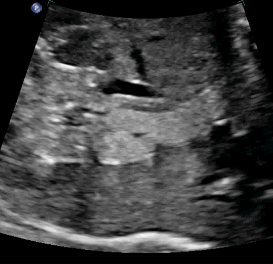

Large Definitive Adrenal Mass

Above. Longitudinal view. Large 3.4 X 2.8 cm mass, hyperechoic structure with small cystic-like clusters. Possibilities include neuroblastoma.

Above. Transverse view. Same patient as immediately above. Large echogenic adrenal mass, possible neuroblastoma versus sub-diaphragmatic pulmonary sequestration. Feeding vessel was not demonstrated.